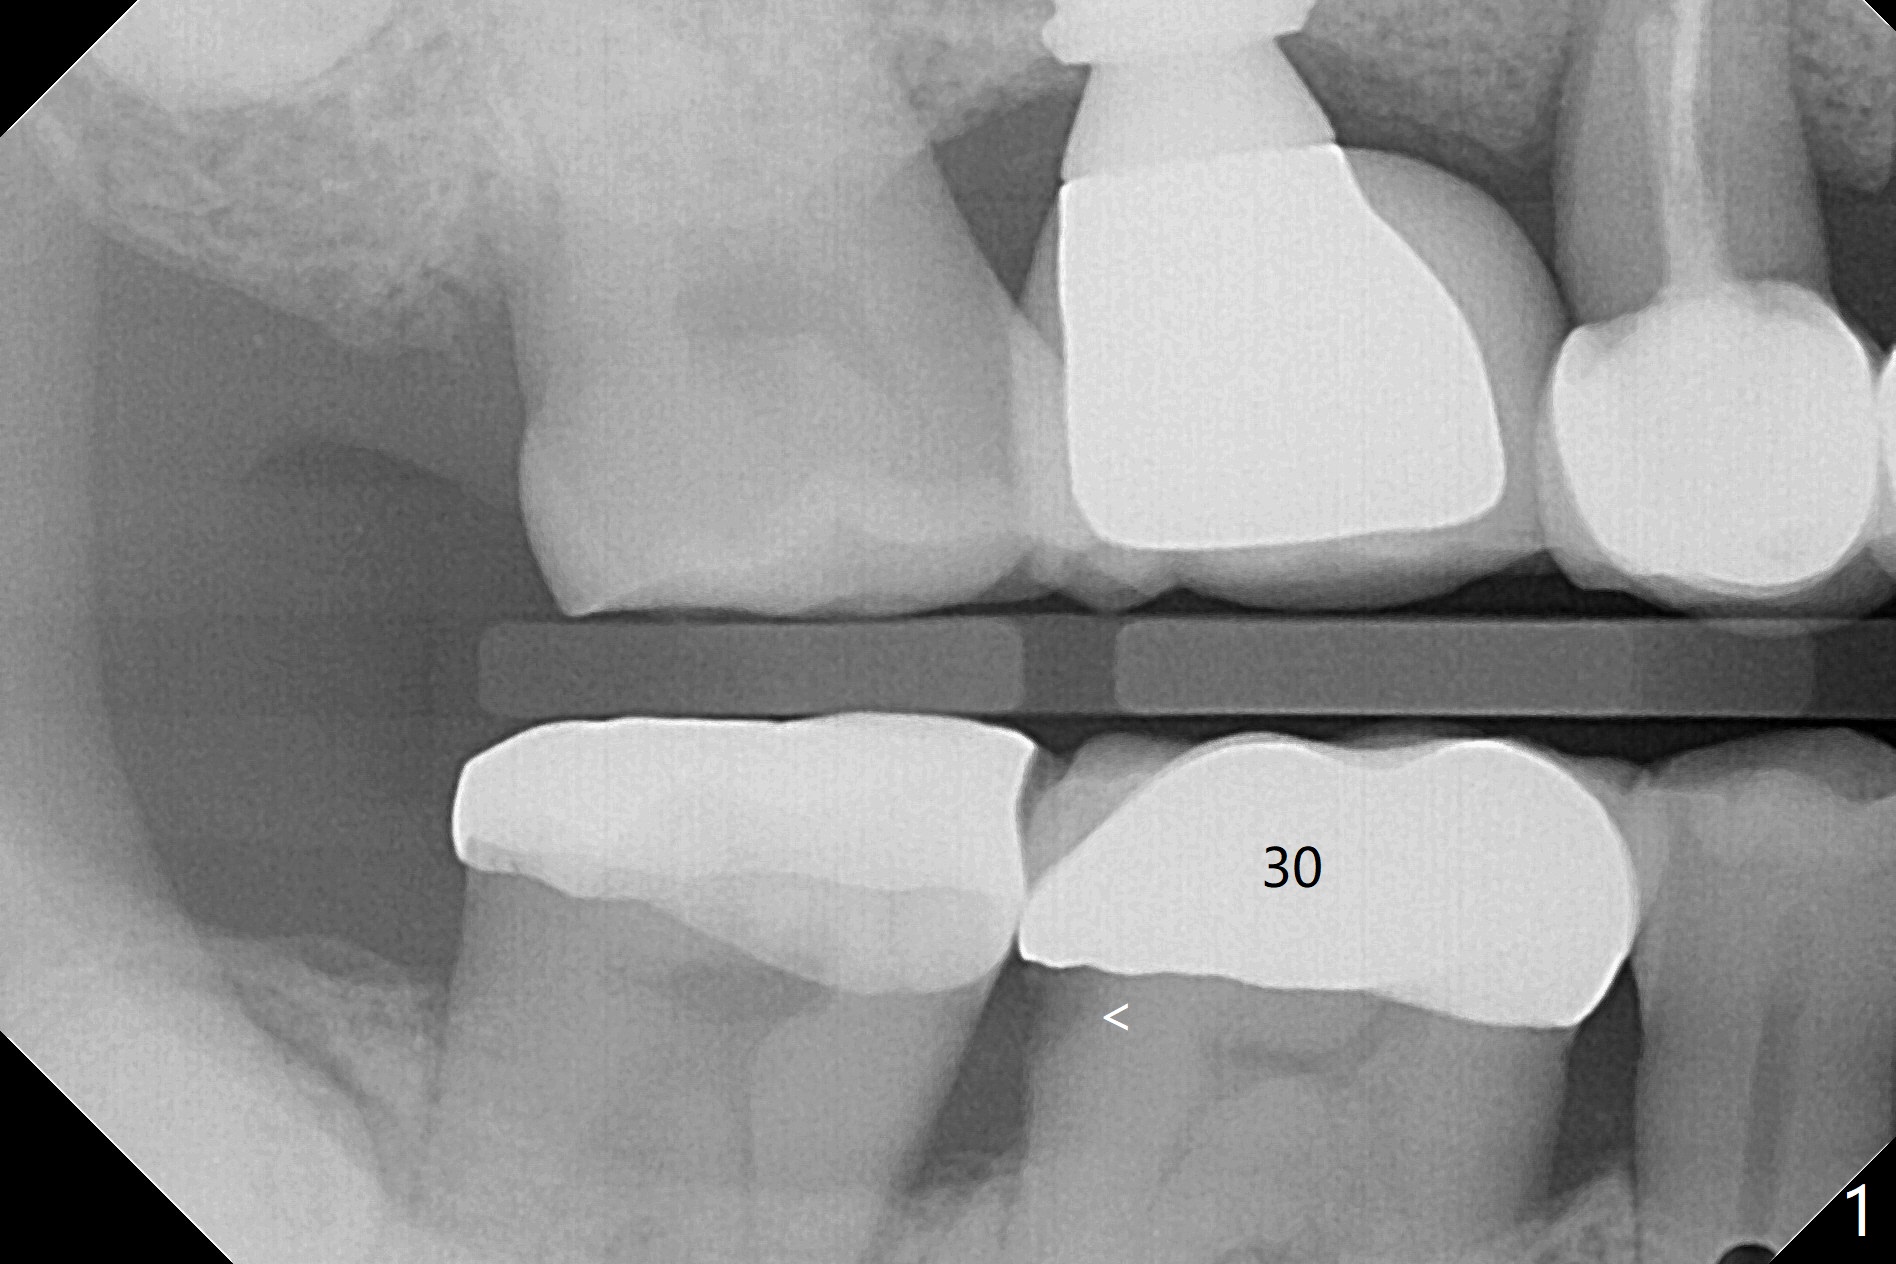

Early Intervention for Open Margin to Prevent Tooth Fracture

A 53-year-old man returns for #30 crown redo with distal open margin (Fig.1-3 arrowhead) after #4 implant. In addition to the distal margin caries, there is buccal one after removal of the existing crown. Composite build up is done for the buccal cavitation, whereas heavy chamfer margin is prepared distal. BW is taken immediately before cementation with open margin (Fig.4 ^). The latter disappears when the crown is cemented with pressure (Fig.5 arrow).